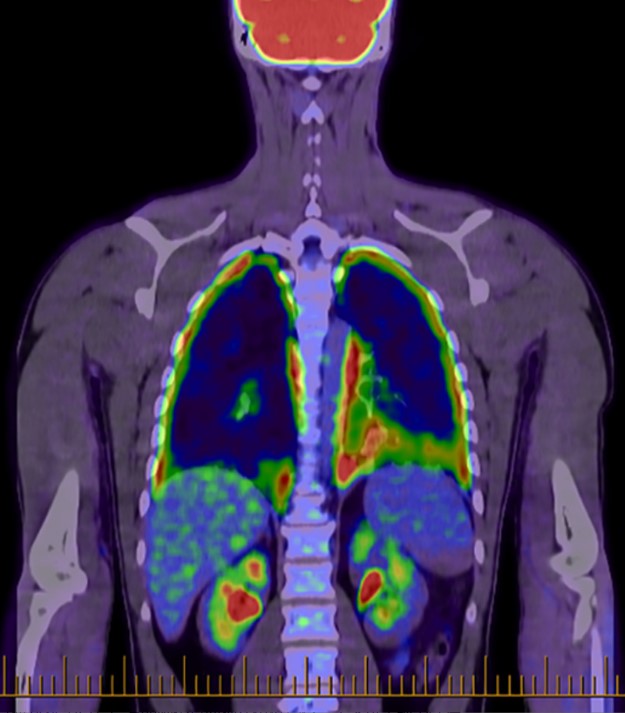

Fig.1 Whole-body positron emission tomography scan with diffuse pleural fluorodeoxyglucose uptake.1,3